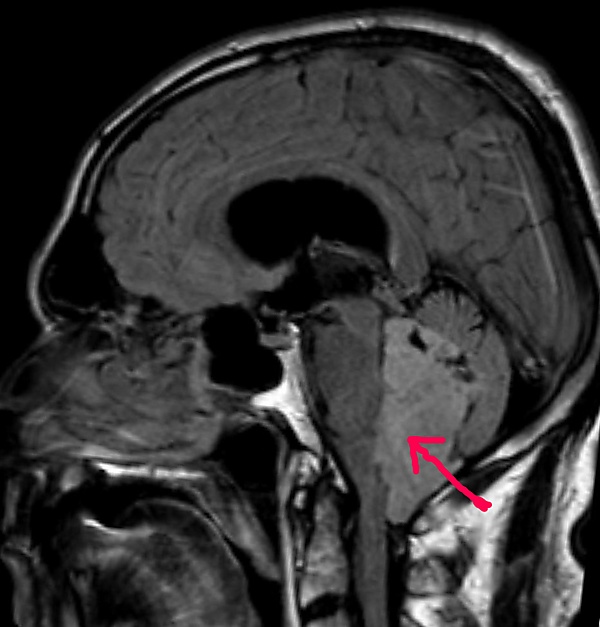

МРТ больного с эпендимомой IV желудочка в Т1-взвешенном режиме. Опухоль отмечена стрелкой

В типичных случаях на МРТ эпендимомы видны в виде объёмных образований, которые заполняют, а иногда и полностью тампонируют полость IV желудочка и распространяются в большую затылочную цистерну или боковую цистерну моста. Солидная часть новообразования на Т1-взвешенных томограммах выглядит изо- или даже гипоинтенсивной и гиперинтенсивной на Т2-взвешенных томограммах[24].

Дифференциальная диагностика эпендимом с другими глиомами основывается в основном на их локализации и топографии, а не на различиях интенсивности сигнала или степени контрастного усиления[25]. Кистозный компонент имеет гипоинтенсивный сигнал на Т1-взвешенных МРТ и гиперинтенсивный по отношению к мозгу на изображениях, взвешенных по Т2. Гетерогенность структуры опухоли обусловлена наличием кист, петрификатов, опухолевой сосудистой сети. После введения контраста отмечается негомогенное усиление средней интенсивности[26]. Дифференциальную диагностику эпендимом боковых желудочков необходимо проводить с медуллобластомами и астроцитомами[23].